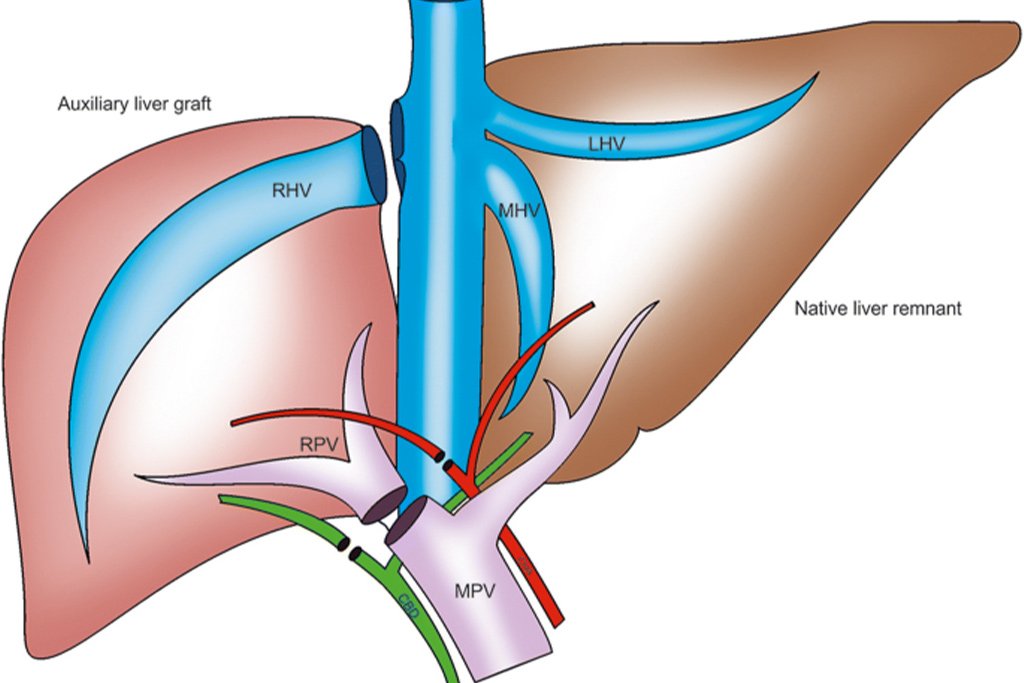

Auxiliary Liver Transplant

- A portion of the donor liver is transplanted while the diseased liver remains partially functional

- Suitable for acute liver failure cases where native liver function may recover